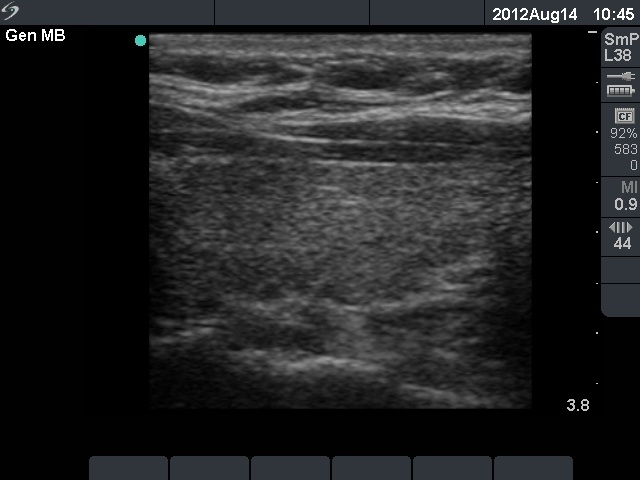

First examination (1st and 2nd rows of images):

Clinical presentation: a 45-year-old woman was referred with typical complaints of subacute thyroiditis: fever, pain in the region of the left thyroid lasting for 4 weeks.

Palpation: the left thyroid was hard and painful, while the right thyroid was moderately firm and not tender.

Functional state: moderate degree of hyperthyroidism with TSH-level 0.001 mIU/L, FT4 35.1 pM/L. ESR 70 mm/H, CRP 21.7 mg/L.

Ultrasonography: there were multiple hypoechogenic areas with blurred borders within echonormal background in the left thyroid. The vascularization was decreased. The right thyroid was intact and had normal vascularization.

Cytological diagnosis: subacute, granulomatous de Quervain's thyroiditis.

Suggestion: steroid therapy. The complaints of the patient suddenly stopped within 24 hours after the steroid intake.